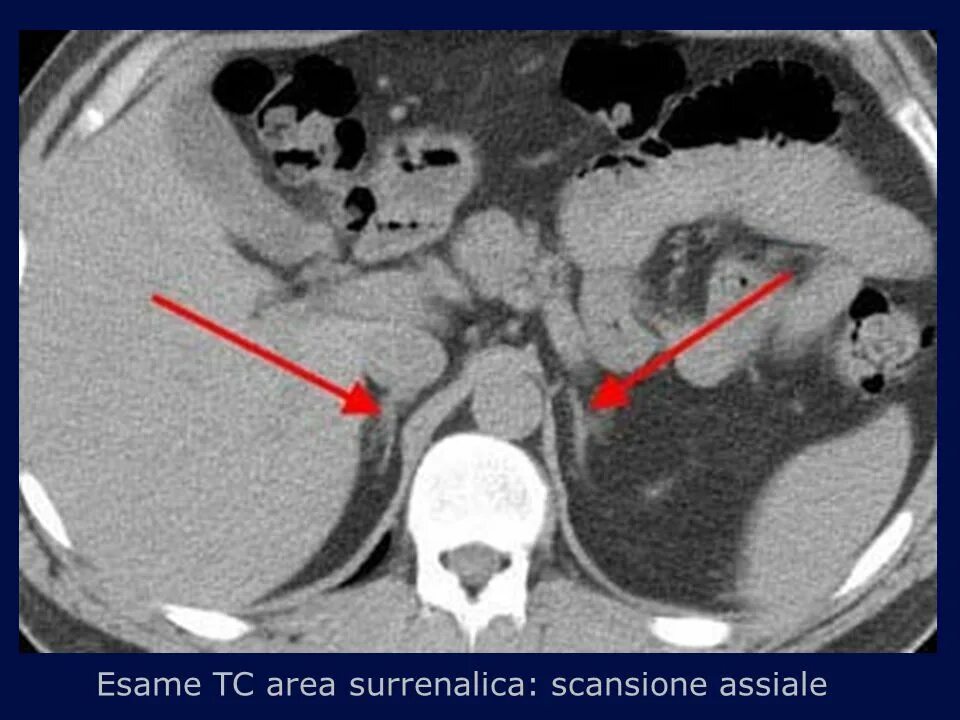

Подготовка к узи почек и забрюшинного пространства